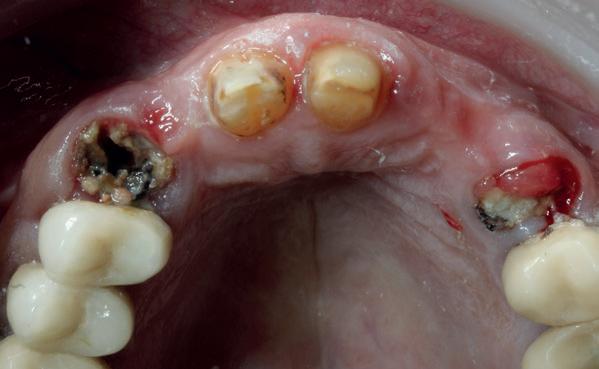

Er worden lichtfoto’s gemaakt van het gebit waarop blijkt dat enkel een aantal incisieven in boven- en onderkaak onbehandeld zijn (zie lichtfoto’s bij intake). De residentie lijkt vrijwel geheel gekroond en/ of overbrugd. Er is sprake van gedateerd kroon- en brugwerk waarbij kroonranden met de jaren bloot zijn komen te liggen en er is sprake van secondaire cariës. Daarnaast stel ik een fors verlies van verticale hoogte van de aanwezige processus in alle vier de kwadranten vast. Is hier sprake geweest van een verleden met ernstige parodontitis?

1. Gedateerd kroon- en brugwerk; fors aanhechtingsverlies zijdelingse elementen.

2. Ernstige parodontale afbraak verspreid aanwezig; (sec.)cariës

Op basis van de eerste indruk die ik krijg tijdens het globale klinische onderzoek, wordt een orthopantamogram (zie OPT bij intake) gemaakt. Samen met de meegestuurde röntgenopnames (zie solo’s) wordt eenvoudig vastgesteld dat er sprake is van ernstig botverlies, bijvoorbeeld bij de 16, 17 en de 18 tot 100% verlies aan alveolair bot. De 16 vertoont daarnaast een grote peri-apicale laesie. In het eerste kwadrant lijkt daarom alleen de 12 een goede prognose te hebben. De 12 vormt samen met de 16 een vierdelige brug en deze constructie lijkt dus verloren. Overigens vermoed ik dat de 12 eigenlijk een cuspidaat is en ontbreekt de 12 (agenesie). Daarnaast worden sterk verdiepte ontstoken pockets geconstateerd bij de 16, 17 tot 12 mm en zijn de elementen sterk verhoogd mobiel. De 11 lijkt als enige element van de gehele dentitie niet te zijn behandeld.

In het tweede kwadrant ziet de situatie er in eerste instantie röntgenologisch veel beter uit. Een vierdelige brug rust op twee pijlers: de 24—27. Ook hier is sprake van vermoedelijk agenesie van de 22. Bij nader onderzoek blijkt diepe cariës onder de kroon

de kaak. Voor een accuratere diagnostiek is een CBCT-scan nodig.

aanwezig bij de 27 en is dus ook de brug in het tweede kwadrant verloren. Daarnaast zijn er verdiepte ontstoken pockets bij de 26, 27 met gevorderd aanhechtingsverlies (pockets tot 8 mm) wat bevestigd wordt in de opgemaakte parodontiumstatus (zie intake status). Verder zijn de 21 en de 23 behandeld met composiet waarbij de 23 is omgebouwd tot een laterale incisief. Als we kijken naar het derde kwadrant dan wordt 10 mm aanhechtingsverlies bij de 35 geconstateerd (8mm pocket met 2mm recessie). De brug in het derde kwadrant vindt zijn houvast op de 34, 35; beide elementen zijn endodontisch behandeld. De 35 heeft een zeer matige prognose ten gevolge van de ernstige mate van alveolair botverlies en voldoet niet meer als pijlerelement. Hierdoor is de prognose van de brug 34, 35—38 ook zeer matig en is de brug dus verloren. De overspanning van drie elementen met een brug op twee pijlers waarbij de ene pijler een endodontisch behandelde premolaar (34) betreft en de 38 een enkele korte wortel als enige gezonde pijler functioneert, voldoet de brug mechanisch niet meer als duurzame prothetische oplossing. Zowel de 32 als met name de 33 zijn fors met composiet geres-

taureerd (zie klinische foto’s) wat waarschijnlijk in de nabije toekomst een endodontische behandeling nodig maakt. De prognose van beide elementen is daarom dubieus.

Dat de brug in het vierde kwadrant nog niet is losgekomen op de pijlers, is een wonder. De zesdelige brug is vervaardigd op vier pijlers: 43, 44, 45 en de 48. Zowel op de meegestuurde solo als op de OPT is secondaire cariës zichtbaar onder de kroon van de 44. Bij de 45 is een poging gedaan om secondaire cariës cervicaal te behandelen met composiet. Parodontaal is de 45 mogelijk het slechtst eraan toe. De 45 vertoont zeer verdiepte en ontstoken pockets tot 9 mm met gingivarecessie tot 2-4 mm. Er is dus sprake van aanhechtingsverlies tot 11 mm en röntgenologisch lijkt er sprake te zijn van een angulair defect bij zowel de 44 als de 45. Beide elementen zijn endodontisch behandeld. De prognose van beide elementen is dus slecht.